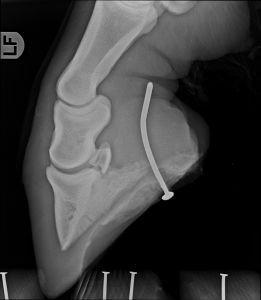

Rozdíl je obrovský. Není to tak dávno, kdy rentgen mělo jen pár veterinářů a snímky jezdili vyvolávat do temné komory. V dnešní době vlastní přenosný rentgen a ultrazvuk již naprostá většina terénních veterinářů zabývajících se ortopedií koní. Výsledky těchto vyšetření tak máme okamžitě, na místě a v nesrovnatelně vyšší kvalitě, než tomu bylo v minulosti. Tyto zobrazovací metody pak napomáhají dobrat se ke správné a přesné diagnóze.

Není již výjimkou referovat cennější pacienty na magnetickou rezonanci, výpočetní tomografii a scintigrafii, což také velmi napomáhá porozumět některým patologickým procesům. Tento komfort však může svádět k opomíjení důkladného klinického a ortopedického vyšetření a mnoho pacientů pak má rentgeny “od hlavy až k patě” bez jakékoliv diagnózy.

Na obrázku 1 výš – hříbě před léčbou, na obrázku 2 – totéž hříbě po léčbě

Dalším problémem je mylná představa některých kupujících, že kůň s „čistými rentgeny“ musí být zdravý a kůň s nálezem na rengenu není do sportu. Rentgenologické vyšetření sice napomůže míru rizika odhadnout, ale je třeba rentgeny vždy posuzovat vzhledem ke klinickému stavu, ale také věku a výkonnosti koně. Samotné rentgenologické vyšetření je velmi zavádějící, protože i koně s „čistými rentgeny“ nemusí skoro chodit a naopak kůň s významnými nálezy může do 20 let úspěšně sportovat.